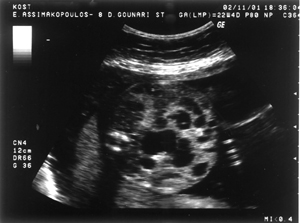

Εικόνα 2. Παρόμοια εικόνα

διάτασης του εντέρου του εμβρύου, από άλλη τομή, στις 22 εβδομάδες της κύησης

(εικόνα 1).

και βρέθηκε φυσιολογικός καρυότυπος θήλεος εμβρύου (46ΧΧ). Στις 22 εβδομάδες

στην εξέταση ρουτίνας του δευτέρου τριμήνου για εμβρυϊκές ανωμαλίες (υπερηχογράφημα

18-23 εβδομάδων) διαπιστώθηκε εκτεταμένη διάταση του εντέρου, με πολλαπλές εντερικές

έλικες γεμάτες υγρό στην κοιλιακή χώρα (εικόνες 1,2). Δεν σημειώθηκαν παθολογικά